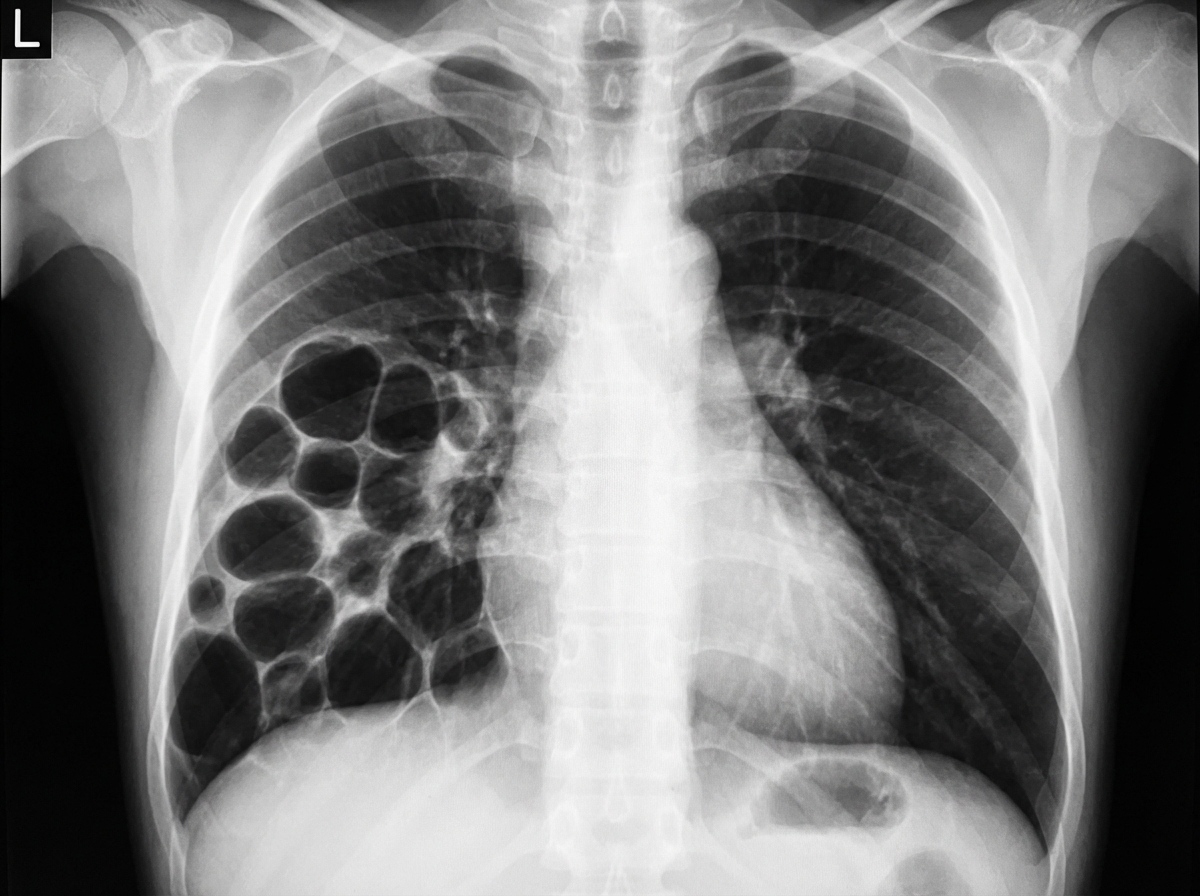

A 3-year-old child presents with respiratory distress and a history of recurrent respiratory infections. Based on the provided imaging, what is the most likely diagnosis?

Explanation: ***CPAM (Congenital Pulmonary Airway Malformation)*** - The imaging shows **cystic lesions** within the lung parenchyma, which are characteristic of CPAM. These lesions can cause **respiratory distress** and predispose to **recurrent infections**. - The age of the child (3 years old) and the history of recurrent respiratory infections are consistent with CPAM, as these malformations often manifest with symptoms in early childhood. *Lung abscess* - A lung abscess typically presents as a **cavity with an air-fluid level** and surrounding consolidation, usually in a single, well-defined area. - While recurrent infections can occur, the widespread cystic appearance on imaging makes an abscess less likely than CPAM. *Pyopneumothorax* - Pyopneumothorax is characterized by the presence of both **pus and air in the pleural space**, leading to a visible air-fluid level that occupies the pleural cavity. - The imaging does not show evidence of gas and fluid within the pleural space, nor the typical chest wall separation seen in pneumothorax. *CDH (Congenital Diaphragmatic Hernia)* - CDH involves the **herniation of abdominal contents** into the chest cavity, displacing lung tissue and often causing severe respiratory distress from birth due to pulmonary hypoplasia. - The images show cystic changes within the lung parenchyma, not abdominal organs in the chest, and the age of presentation makes a new diagnosis of uncorrected CDH less likely, as it usually presents as a neonatal emergency. *Pulmonary sequestration* - Pulmonary sequestration is a congenital malformation characterized by **non-functioning lung tissue with aberrant systemic arterial supply**, typically from the aorta. - While it can present with recurrent infections, the imaging typically shows a **solid or mixed solid-cystic mass**, often in the lower lobes with visible feeding vessels on contrast imaging, rather than the predominantly multicystic appearance seen in CPAM.